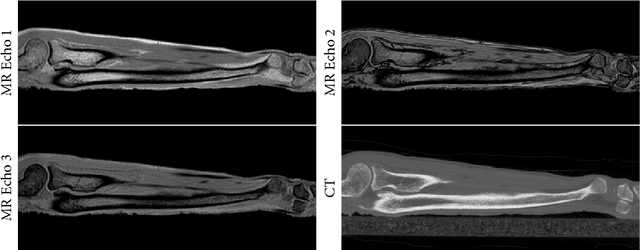

Abstract:Purpose: To assess the feasibility of deep learning-based high resolution synthetic CT generation from MRI scans of the lower arm for orthopedic applications. Methods: A conditional Generative Adversarial Network was trained to synthesize CT images from multi-echo MR images. A training set of MRI and CT scans of 9 ex vivo lower arms was acquired and the CT images were registered to the MRI images. Three-fold cross-validation was applied to generate independent results for the entire dataset. The synthetic CT images were quantitatively evaluated with the mean absolute error metric, and Dice similarity and surface to surface distance on cortical bone segmentations. Results: The mean absolute error was 63.5 HU on the overall tissue volume and 144.2 HU on the cortical bone. The mean Dice similarity of the cortical bone segmentations was 0.86. The average surface to surface distance between bone on real and synthetic CT was 0.48 mm. Qualitatively, the synthetic CT images corresponded well with the real CT scans and partially maintained high resolution structures in the trabecular bone. The bone segmentations on synthetic CT images showed some false positives on tendons, but the general shape of the bone was accurately reconstructed. Conclusions: This study demonstrates that high quality synthetic CT can be generated from MRI scans of the lower arm. The good correspondence of the bone segmentations demonstrates that synthetic CT could be competitive with real CT in applications that depend on such segmentations, such as planning of orthopedic surgery and 3D printing.